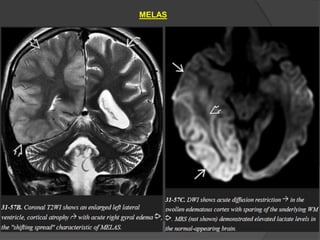

MELAS

Mitochondrial encephalomyopathy with lactic acidosis and stroke-like

episodes (MELAS)

The clinical triad of lactic acidosis, seizures, and stroke-like episodes is the

classic presentation.

Acute MELAS –

often shows swollen T2/FLAIR hyperintense gyri.

The underlying WM is normal

The cortical abnormalities cross vascular distribution territories,

distinguishing MELAS from acute cerebral infarction.

The parietal and occipital lobes are most commonly affected.

Gyral enhancement on T1 C+ is typical.

MRA shows no evidence of major vessel occlusion.

Chronic MELAS-

shows multifocal lacunar-type infarcts,

symmetric basal ganglia calcifications,

WM volume loss, and progressive

atrophy of the parietooccipital cortex.

MRS

Two-thirds of cases show a prominent lactate "doublet" at 1.3 ppm in

otherwise normal-appearing brain.

One-third of cases show no evidence for elevated lactate levels in the

brain parenchyma but may demonstrate a lactate peak in the ventricular

CSF.